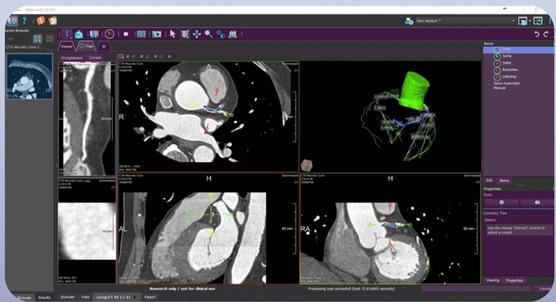

October 9, 2017 — Medis has released a new version of its QAngio CT (computed tomography), which can now be launched from the Medis Suite imaging platform. QAngio CT v3.1 provides a detailed plaque burden analysis of the coronary system with comprehensive results.

Viewing

- Viewing 3-D CTA series, double oblique viewing, MPR, MIP, slabbed MIP, VR; and

CTA analysis workflow

- Fully automatic extraction of the complete coronary tree;

- Semi-automatic editing of coronary tree;

- Automatic labeling of the segments in the coronary tree with anatomical names;

- Analyze multiple vessels at the same time;

- A two-step contour detection approach per vessel for both lumen and vessel contours:

- Longitudinal detection: provides quick overview of border and allows easy corrections which will propagate to the transversal step.

- Transversal detection: Based on the longitudinal contours and corrections.

- Edit contours in longitudinal and transversal images simultaneously; and

- Flexible lesion detection and definition using synchronized views of the vessel data (stretched MPR, curved MPR, graphs).